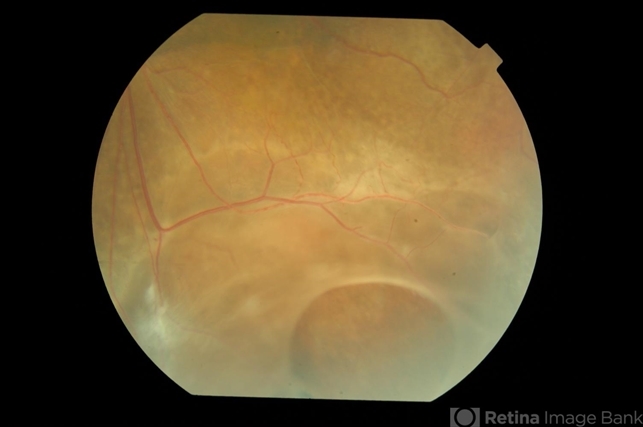

- Retinoschisis

- juvenile retinoschisis, retinal break

- Fundus photograph of left eye of a 9-year-old boy with juvenile retinoschisis with large inner retinal break .